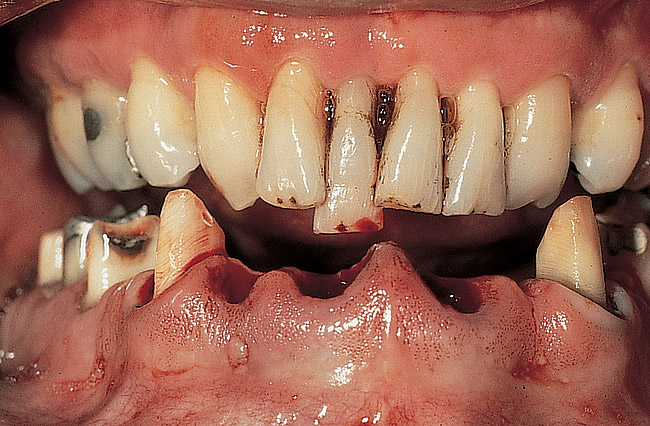

Figure 12  Preoperative facial view demonstrating maximum tooth display.

Figure 12

Figure 13  Preoperative intraoral facial view.

Figure 13